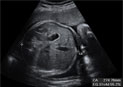

Ecografía del tercer trimestre: Hueso del fémur

Medir este hueso ayuda a averiguar la edad gestacional

El fémur es el hueso más largo del feto, por eso se utiliza en la estimación de la edad gestacional del bebé. Al ser el hueso más largo, el error de medición se minimiza. En realidad no medimos el hueso en toda su longitud, sino su parte osificada. En la imagen se aprecia con nitidez el hueso, así como la medición, tomada entre dos puntos que se señalan con una cruz.

Ecografía del hueso del fémur en el tercer trimestre de embarazo